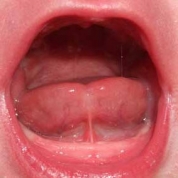

Короткая уздечка языка у ребенка

На фото: короткая уздечка языка у ребенка

Подъязычная уздечка в норме имеет длину не менее 8 мм и прикрепляется примерно на середине между корнем и кончиком языка. Маленькая уздечка обычно выглядит складкой на слизистой оболочке, приросшая на всем своем протяжении к языку или подъязычному пространству.